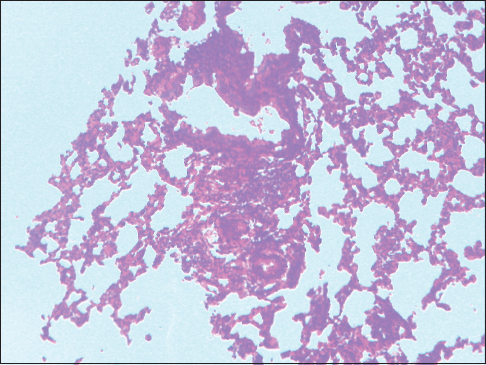

Figure 2: Formalin pigment in a section of the lungs, ×100